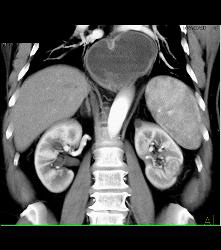

Hypervascular Left Renal Cell Carcinoma